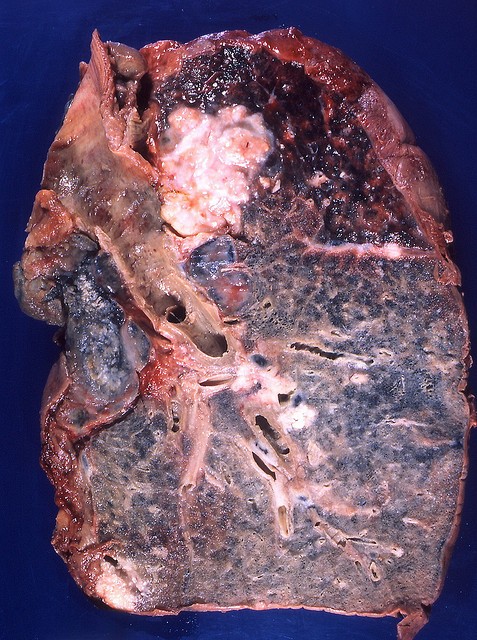

【閲覧注意】タバコ吸ってるやつ、ヤバいぞ・・・(画像)

gif_animation 「肺がん」を含む、タバコを吸っている人々の肺の画像。[7]images

Lung cancer